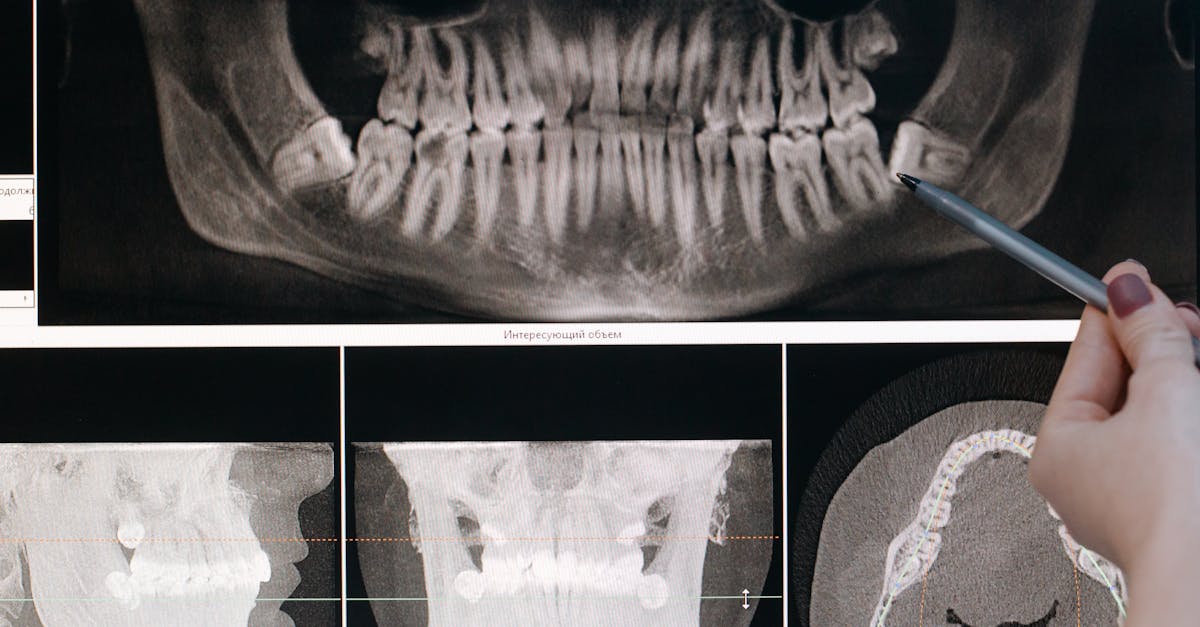

8. Dental and Occlusal Asymmetries - Orthodontic and Surgical Considerations

Significant dental and occlusal asymmetries that affect facial appearance and function can indicate underlying skeletal abnormalities, developmental disorders, or pathological conditions that may require comprehensive medical and dental evaluation. These asymmetries often manifest as uneven tooth alignment, midline discrepancies, or differences in jaw size and position that create noticeable facial imbalance. While minor dental irregularities are common and primarily cosmetic concerns, severe asymmetries can indicate underlying issues such as hemifacial microsomia, condylar hyperplasia, ankylosis of the temporomandibular joint, or other craniofacial abnormalities that require multidisciplinary treatment. Hemifacial microsomia, the second most common facial birth defect after cleft lip and palate, causes underdevelopment of one side of the face, affecting the jaw, ear, and surrounding structures, resulting in significant facial asymmetry and functional impairments. Condylar hyperplasia involves excessive growth of one mandibular condyle, causing progressive facial asymmetry, dental midline shifts, and occlusal problems that can continue into adulthood if not properly managed. Dental asymmetries can also result from early loss of primary teeth, trauma, tumors, or infections that affect normal dental development and eruption patterns. The functional implications extend beyond appearance to include difficulties with chewing, speaking, and maintaining proper oral hygiene, potentially leading to dental decay, gum disease, and temporomandibular joint problems. Evaluation requires comprehensive dental and orthodontic examination, detailed medical history, and often specialized imaging such as cephalometric radiographs, CT scans, or 3D imaging to assess both dental and skeletal relationships. Treatment planning may involve orthodontic therapy, oral surgery, or combined orthodontic-surgical approaches to address both functional and aesthetic concerns. Early intervention is often crucial for optimal outcomes, particularly in growing patients where growth modification techniques may be employed to guide facial development.